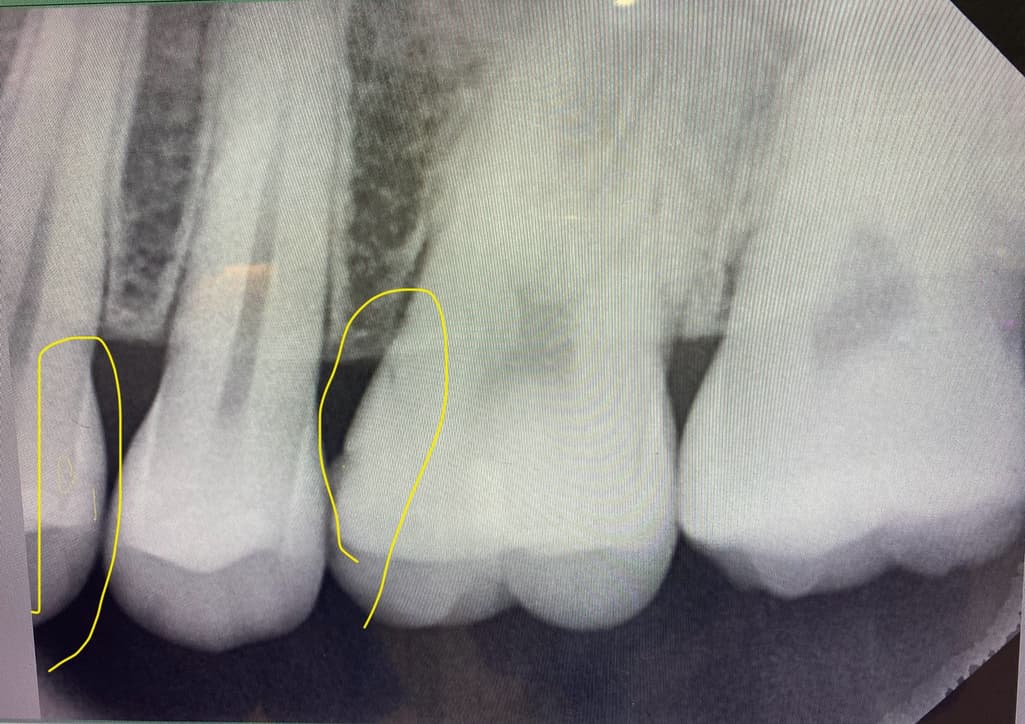

치과 한곳에서 육안으로 인접면 충치와 어금니 2차충치

확인하고 인레이 70만 또는 레진 30만

3곳 모두 인접면 충치가 보이긴 하지만 증상도 없고

엑스레이, 치근단 사진을 봐도 너무 작아서

6개월 마다 경과를 지켜보자

그리고 2차충치는 안보이고 많이 닳긴했지만 이상 없다